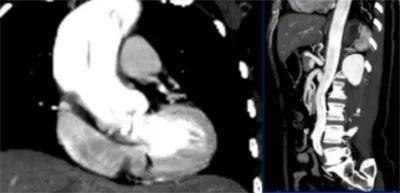

主动脉CTA造影,如下图所示。

1. 主动脉夹层动脉瘤(Stanford A型)

2. 继发性右冠状动脉夹层致右室梗死

行急诊外科手术,术中发现,冠脉呈左优势型,右冠脉全段撕裂。在全麻低温体外循环下行主动脉根部置换(Bentall)+升主动脉置换+半弓置换+冠状动脉旁路移植术(CABG)。手术持续5小时余,创面出血持续15小时余,整个手术时长20多小时,最后患者转危为安,脱离生命危险。